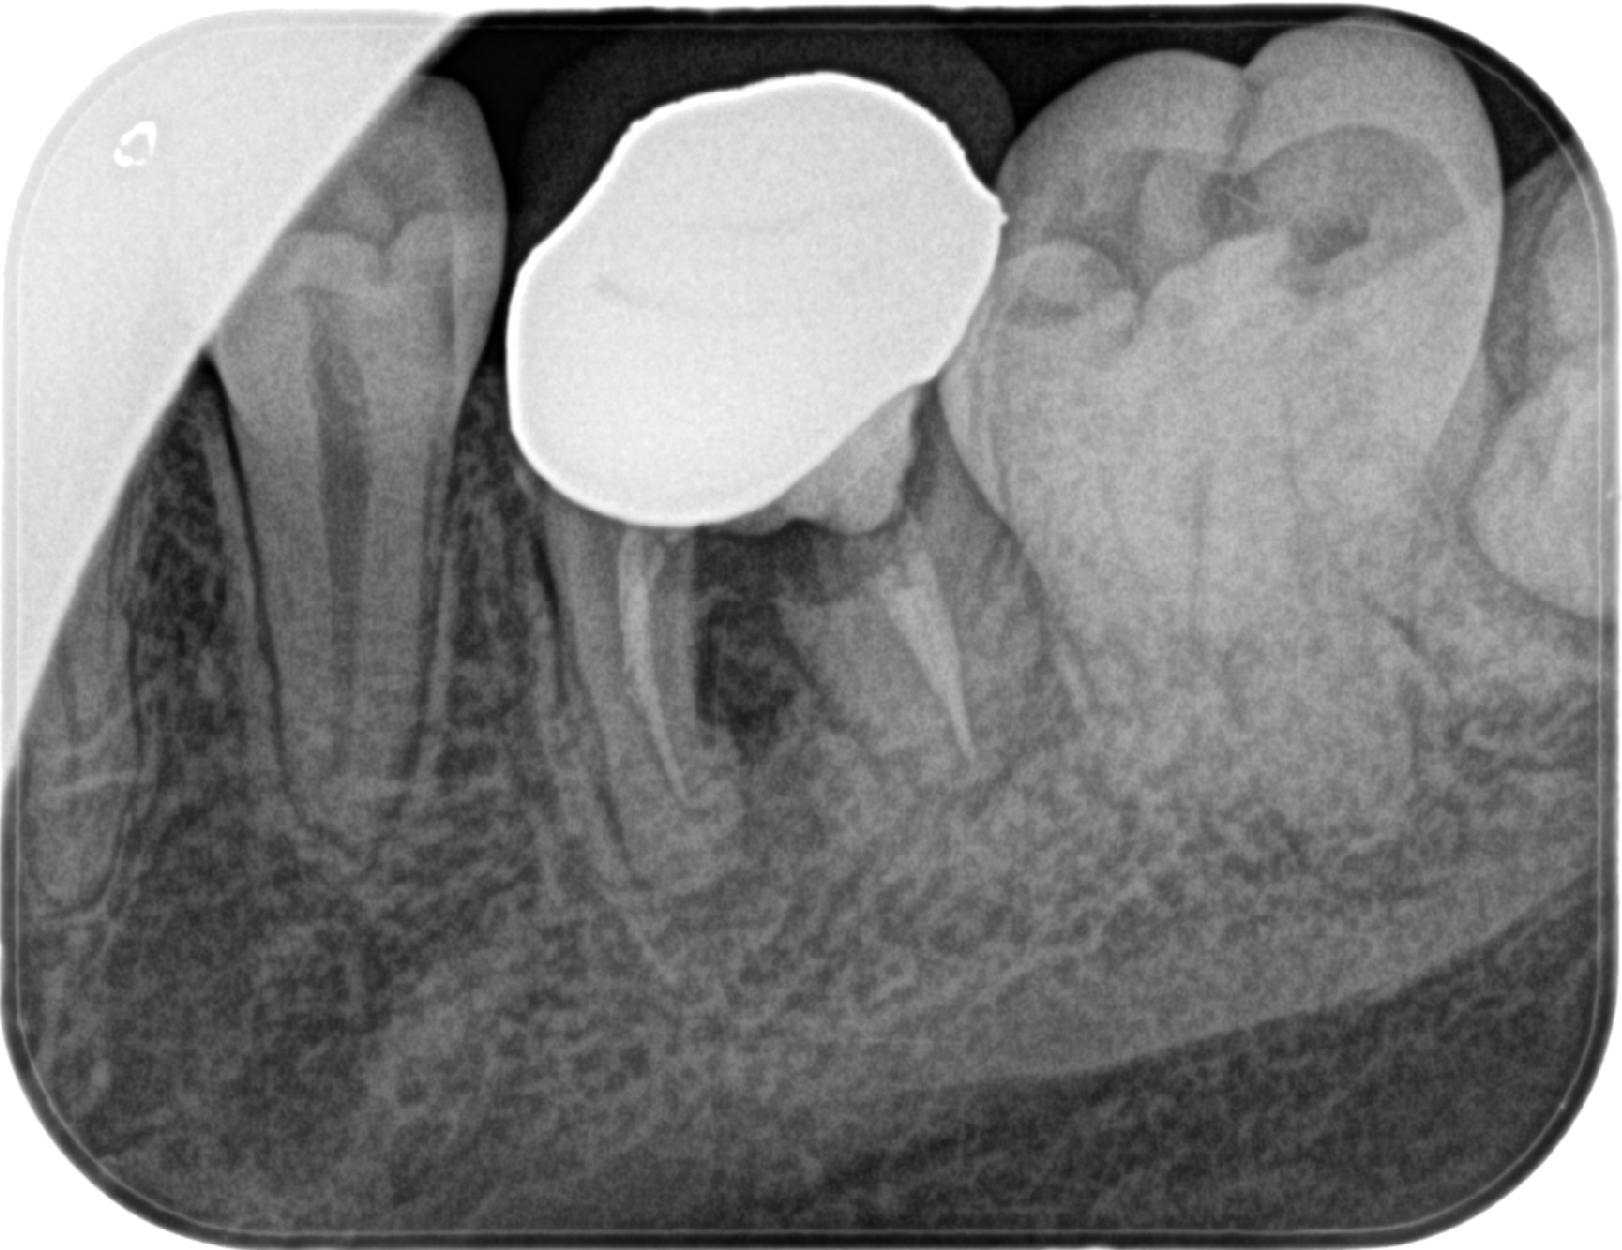

世界でも数多くの歯科医師に選ばれている「ストローマンインプラント」を採用。先進設備による精密な検査・診断と丁寧な処置で、埋入手術による痛みや腫れを減らし、安定性の高い長持ちするインプラント治療を提供しています。